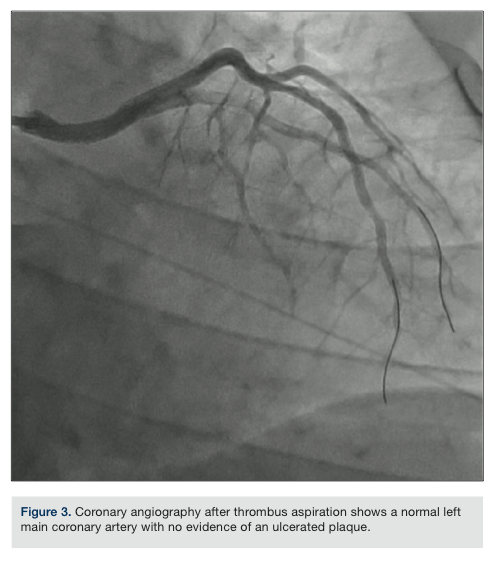

To revascularize the left coronary system, a 7 French (Fr) XB 3.5 guide catheter (Cordis) was used to selectively engage the LM coronary artery. A Pronto V3 catheter system (Vascular Solutions) was used to successfully aspirate the thrombus manually. Anticoagulation was achieved with intravenous bivalirudin and adjuvant intracoronary abciximab. The patient’s chest pain was completely ameliorated once a significant portion of thrombus in the LM coronary artery was aspirated and we achieved excellent angiographic results after repeated passes with the manual aspiration catheter (Figure 3). The thrombus fragments in the distal LCx were successfully aspirated using the Pronto LP system and fragments of thrombus in the diagonal branch

resolved, with adequate flow restored down these vessels. Coronary flow to the distal LAD, however, was not restored, despite balloon angioplasty and attempts to aspirate thrombus manually with the Pronto LP system. No stents were deployed, because there was no evidence of atherosclerotic stenosis after thrombus aspiration. Left ventriculogram showed a low normal left ventricular ejection fraction (LVEF) of 50% with hypokinesis involving the apical segment of the left ventricle.